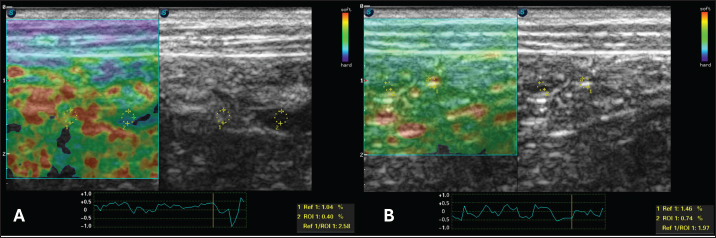

For the static qualitative assessment, the proximal segments of the duodenum and jejunum were analyzed in a longitudinal ultrasound section, and a heterogeneous distribution was found between the dorsal and ventral regions of the intestine, with patterns ranging from predominantly blue with some greenish parts and reddish foci (Fig. 2). To obtain the semiquantitative parameters, the region of interest (ROI) was drawn using the device’s software cursor. Initially, a reference, ROI 1 was obtained in the mesentery adjacent to the intestines, and ROI 2 was drawn in the dorsal region of the duodenum and jejunum. The drawings were similar and circular with the same depth and horizontal direction in the cross-section. The drawings were based on the diameter of the animal’s intestinal mucosa, and the force applied was guided by the elastographic compression wave. The strain ratio (SR) was obtained by calculating the ratio between the ROIs. The values for the duodenum were as follows: ROI 1=1.04 % and ROI=0.4%, with an SR of 2.58 (Fig. 3A). In the jejunum, ROI 1 measured 1.46 %, ROI 0.74 %, and SR 1.97 (Fig. 3B).

Fig. 3. Semiquantitative cross-sectional deformation elastography of the intestine of a dog with intestinal lymphangiectasia. The SR was obtained by evaluating ROI 1 of the mesenteric and ROI 2 of the dorsal region of the intestinal segment. A duodenum with an SR of 2.58 B-Jejunum with an SR of 1.97

After 30 days of treatment, there were no more laboratory changes (Table 2), the CCECAI was reduced to four (Table 1), and the patient no longer had diarrhea and gained weight. In addition, hyperechogenicity of the intestinal mucosa was reduced, and the values for elastography of the duodenum were as follows: ROI 1 1.61 % and ROI 0.99 %, with an SR of 1.62 (Fig. 5A). In the jejunum, ROI 1 measured 0.29 %, ROI 0.25%, and SR 1.14 (Fig. 5B).

Regarding elastographic aspects, no directly comparable veterinary studies have been conducted because there is no description of the strain elastography technique in dogs with this disease. A single analogous study provided reference data on the healthy jejunal mucosa of 60 dogs using shear wave elastography (Spużak et al., 2019). In this study, the mean values of the healthy animals were lower than those of the dogs with PLE. We therefore conclude that the stiffness of the intestinal mucosa is likely to increase, regardless of the elastography technique used. We suggest that this report serves as a basis for further research.

In human medicine, the results are similar to those observed in this report. Intestinal inflammation leads to an increase in the hardness rates seen on strain elastography, and after treatment, these parameters are reduced (Gabbiadini et al., 2021). Therefore, they are used for follow-up and as predictors of fibrosis. Despite the similarity, we did not reveal fibrosis in the duodenal mucosa.